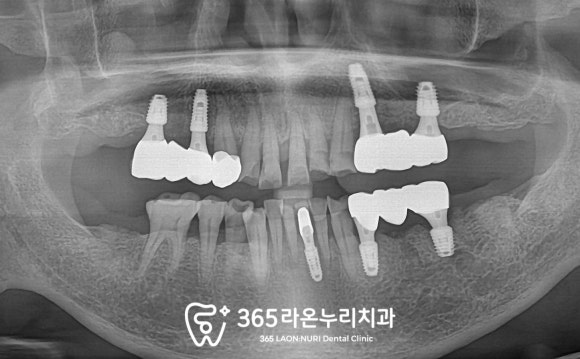

■ 5. 보철 수복

모든 진료를 끝내고

최종 보철까지 올라간 모습을 보겠습니다.

잇몸이 부어잇던 곳들은

스케일링을 해드렸기에

며칠만 지나면 예쁜 선홍빛을 되찾으실 거고

전보다 훨씬 단단히

치근을 잡아줄 수 있을 겁니다.

또한 임시치아를 편하게 쓰신 만큼

최종 보철도 음식물 끼임 없고

저작힘도 좋아지실 수 있도록

섬세하게 디자인하여 올려드렸기에

환자께서 매우 만족해하셨습니다.

글 서론에서 말씀드린 것처럼

2개의 치아는 보험 적용 혜택을 드려

합리적인 가격으로 잘 진료받을 수 있도록

해드렸답니다.